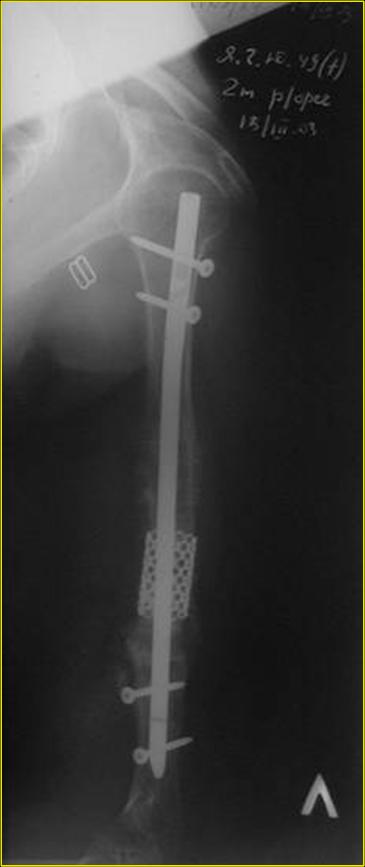

Рентгеновская версия реконструкции хронология в обратном порядке: 1,2

- через 1 год, 3,4 - 2 мес. после операции, 5,6 - после операции.

Движения в полном объеме востановлены к 2 мес. после операции. Если

надо могу  показать мультик. Сейчас уже прошло более 3 лет, больная не

показывается. Успехов ЛАФ.